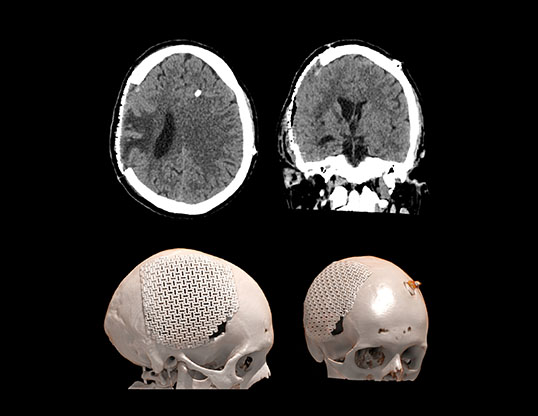

Симптом тонущего лоскута (парадоксальная церебральная грыжа) – является редким и потенциально смертельным осложнением после массивной декомпрессивной краниотомии, проявляющееся в виде инвагинации кожного лоскута в направлении, противоположном участку краниотомии. Триггерным механизмом данного состояния является резкое превышение атмосферного давления над внутричерепным, спонтанно или спровоцированное люмбальной пункцией или гипердренажём цереброспинальной жидкости (после шунтирующих операций, обезвоживания, смена позиции головы).   Данное состояние подлежит неотложной нейрохирургической помощи.

Пациент А., перенесший тяжелую черепно-мозговую травму в ДТП. Состояние после правосторонней гемикраниотомии, эвакуации крупной субдуральной гематомы. Произведена ликворошунтирующая операция с установкой программируемого клапана давления . Через месяц пациент стал предъявлять прогрессирующие неврологические расстройства.

Визуализируется обширная инвагинация кожного лоскута в полость дефекта, смещение срединных структур влево, сдавление САП правого полушария и сглаженность борозд. Причиной данного состояния явилась гиперфункция шунта.

Данному пациенту была произведена краниопластика дефекта черепа, коррекция программируемого клапана давления. Пациент выписан на третьи сутки в удовлетворительном состоянии с полным регрессом неврологической симптоматики.